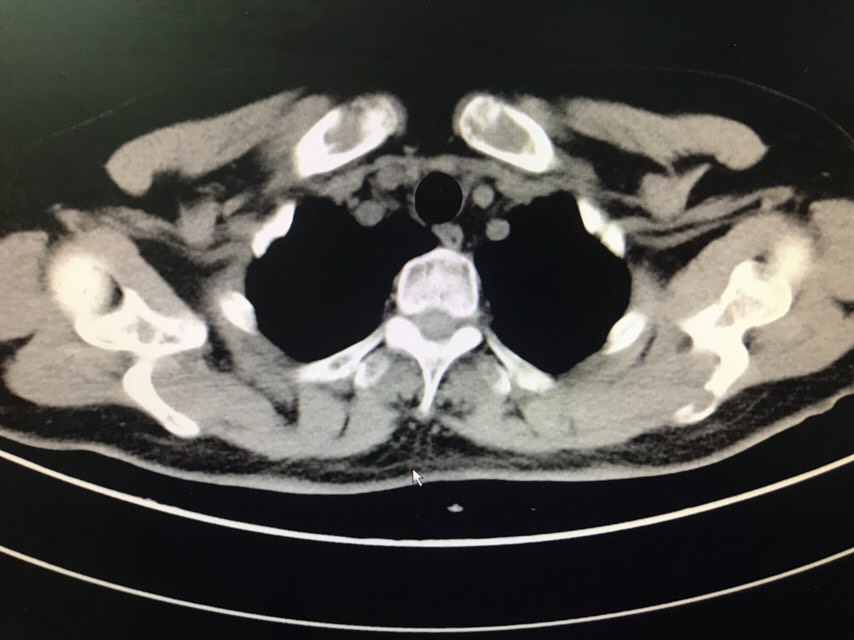

查体无特殊。辅助检查:PET-CT:1、部分颅骨、部分颅底骨质、双侧下颌骨、双侧肩胛骨、双侧锁骨、双侧肱骨上段、双侧多肋骨、胸骨、双侧髂骨、骶1棘突、双侧耻骨部分骨质虫蚀样、溶骨样破坏伴部分破坏骨质FDG代谢异常增高;上述改变考虑多发性骨髓瘤可能性大,请结合临床或右侧肋骨病灶活检。2、甲状腺右叶稍低密度结节影,无FDG代谢异常增高,多为良性病变,建议专科检查;3、双侧口咽壁对称性FDG增高,无确切占位征象,考虑为炎性改变;4、右肾错构瘤;5、脊柱部分骨质增生。骨髓涂片:目前BM示原始浆细胞比例增高8%,成熟红细胞呈缗钱状排列。骨髓活检:取材骨髓组织增生较低下,三系细胞增生均较低。骨髓流式:标本中若表达CD28,不表达CD19、CD117、cLambda、CD27、CD81、CD20、CD45,符合浆细胞肿瘤表型,正常浆细胞占有核细胞娥0.16%;流式检测中浆细胞易被破坏,比例可能低于形态学,请结合形态及免疫固定电泳结果。免疫球蛋白定量:IgG 12.6g/L,IgA 2.05g/L,IgM 0.94g/L,IgE 5.0g/L。血清固定电泳:未见IgG、IgA、IgM、KAP轻链、LAM轻链单克隆成分。尿固定电泳:在LAM区可见一条单克隆KAP轻链成分。血清游离轻链:游离KAP轻链 3800mg/L,游离LAM轻链16.00mg/L、游离KAP轻链/LAM轻链 237.5,尿游离轻链:游离LAM轻链 4100mg/L,游离LAM轻链9.13mg/L、游离KAP轻链/LAM轻链 449.069。